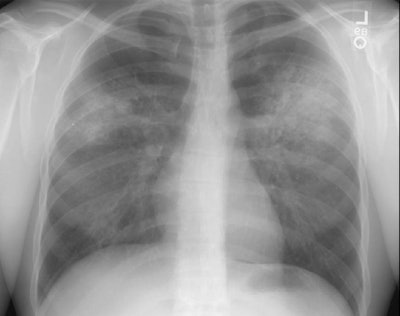

The patient shown in the image below had an extensive travel history and his parents were missionaries in New Guinea. He was referred to the rheumatology service for complaints of polyarthralgia. On exam, additional history revealed complaints of epistaxis, and later hemoptysis. A chest radiograph was obtained.

The chest radiograph demonstrated bilateral consolidations which were primarily confined to the superior segments of the lower lobes and posterior upper lobe segments (click here to see the lateral exam). A PPD was placed and was negative, and the patient was HIV negative. Although plain films of the paranasal sinuses were normal, on direct visualization, mucosal ulcerations were identified. At bronchoscopy, blood was noted within the airways- indicating that the parenchymal abnormalities were likely the result of hemorrhage. Both serum and BAL fluid were C-ANCA positive and a diagnosis of Wegener's was made. However, the open lung biopsy specimen demonstrated both features of Wegener's and an eosinophoilic vasculitis (Churg-Strauss) and the final diagnosis was that of an overlap vasculitis. The patient was treated with steroids and methotrexate with a rapid clearing of the parenchymal abnormalities.